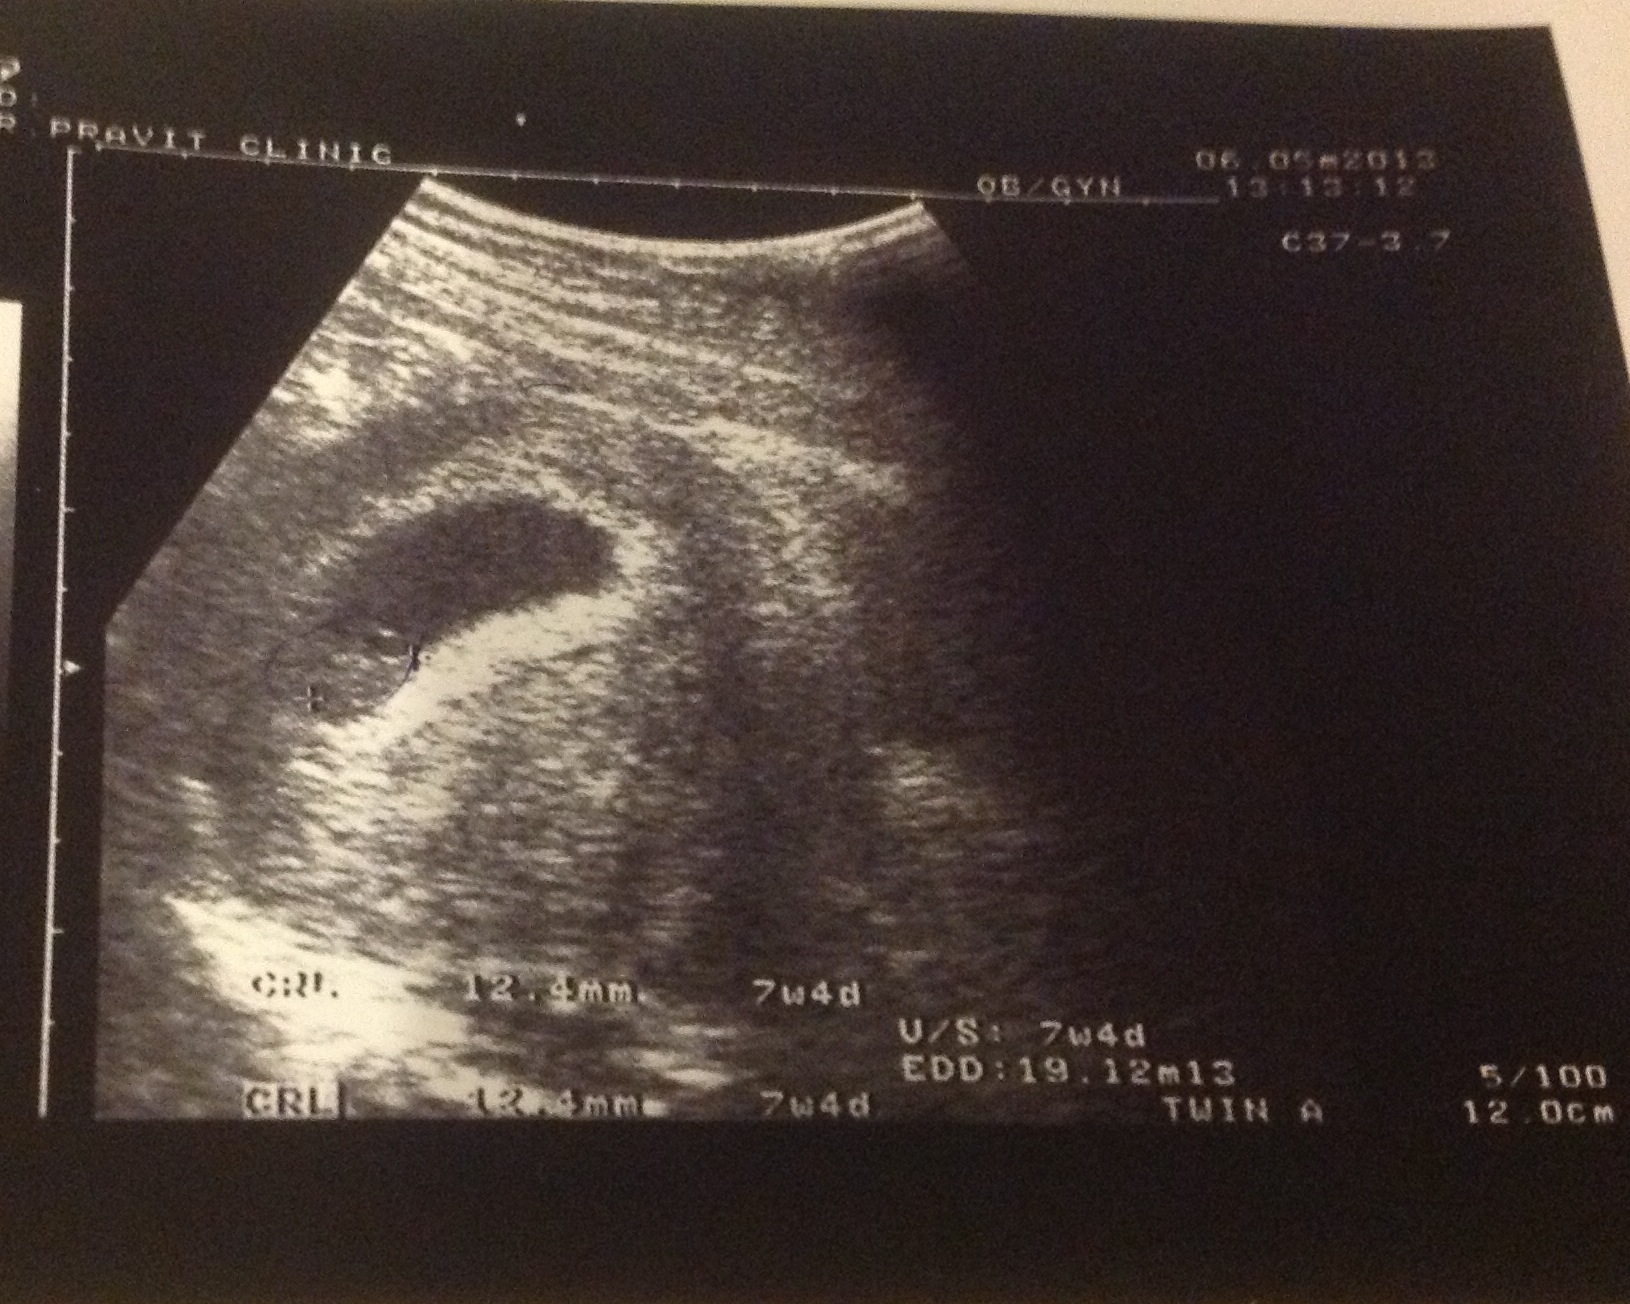

ปรากฎว่ากลับมา ไปอ่านในฟิลม์ มีคำว่า twin อยู่ในฟิลม์ เลยเกิดความสงสัยว่า เอ๋ ท้องแฝดเหรอเนี้ย????

ช่วยดูผลอัตตาซาวน์หน่อยค่ะ สงสัยคำว่า twin a ในฟิลม์หมายถึงแฝดรึเปล่าค่ะ